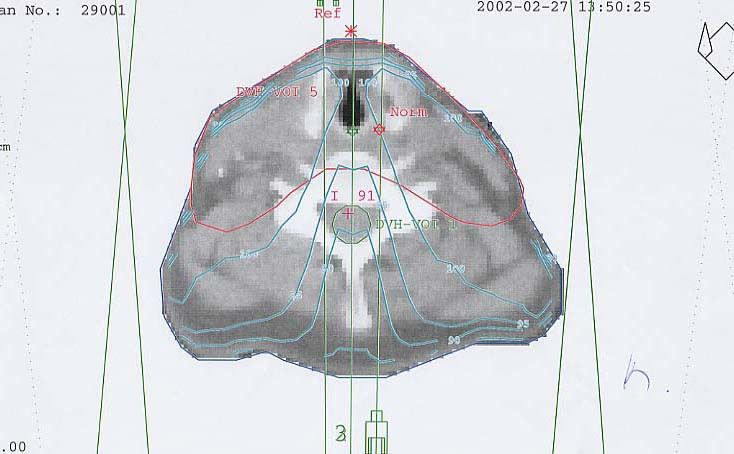

Schilddrüsenkarzinom: Bestrahlungsplan

Bestrahlungspläne